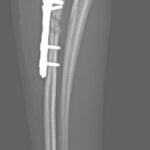

Toy Poodleさんがソファーより転落後に橈骨近位を斜骨折したとの事。1.5 Locking Plateで固定術を実施しました。 しばらく安静が必要です。